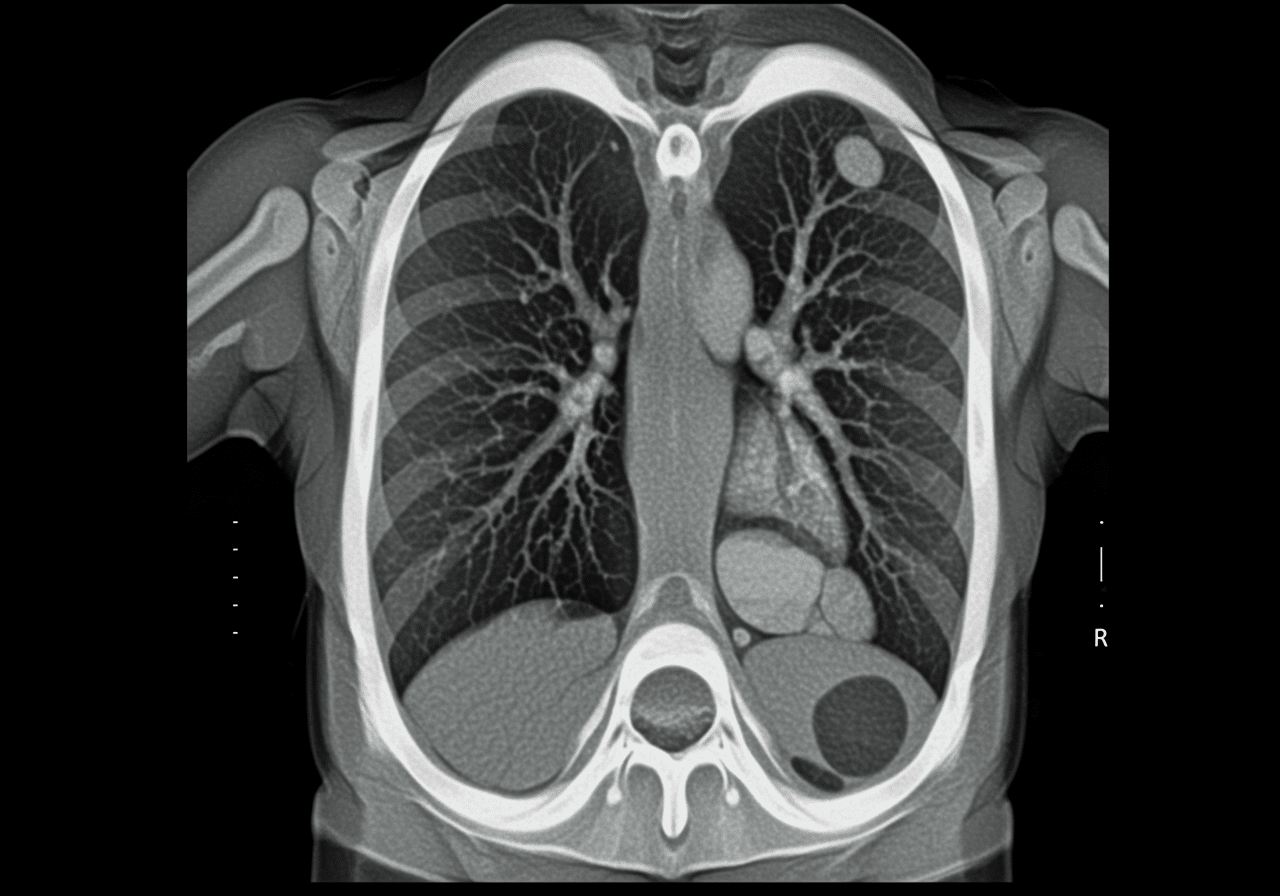

Advanced Chest Imaging Technology: Life-Saving Respiratory Diagnosis

Priority ER's diagnostic capabilities for chest X-ray & CT angiogram for pneumonia, pneumothorax, or PE exceed Joint Commission standards for emergency departments[14], featuring digital portable chest radiography enabling immediate bedside imaging for unstable patients without transport to radiology, multidetector CT with IV contrast pulmonary angiography protocol detecting filling defects in pulmonary arteries with 96% sensitivity, and immediate emergency physician interpretation identifying pneumonia infiltrates, pneumothorax, and pulmonary embolism within 15 minutes. Our emergency physicians trained in chest imaging interpretation apply Wells criteria (clinical probability scoring) and PERC rule (Pulmonary Embolism Rule-out Criteria) determining which patients require CT angiography versus alternative diagnoses, preventing unnecessary radiation while ensuring PE diagnosis when clinically indicated[15]. The integration of right heart strain assessment on CT (RV/LV ratio >1.0) identifies massive PE requiring thrombolytic consideration, while identification of pneumonia complications including empyema, lung abscess, or necrotizing pneumonia guides surgical consultation.

Advanced assessment through our comprehensive diagnostic capabilities provides ventilation-perfusion (V/Q) scanning coordination when CT contraindicated by renal insufficiency or contrast allergy, echocardiography assessing right ventricular dysfunction when massive PE suspected, and bronchoscopy consultation when pneumonia complicated by suspected foreign body aspiration or endobronchial obstruction. For pneumothorax evaluation, our emergency physicians measure pneumothorax size using British Thoracic Society guidelines (distance from lung apex to cupola) determining whether observation, aspiration, or chest tube placement indicated, with immediate intervention for tension pneumothorax presenting with tracheal deviation, hypotension, and absent breath sounds requiring needle decompression before radiographic confirmation. This comprehensive approach explains why the American College of Radiology appropriateness criteria mandate chest X-ray as first-line imaging for pneumonia and pneumothorax, with CT angiography reserved for PE diagnosis providing definitive visualization of thrombus location and burden guiding anticoagulation versus thrombolytic therapy.

CT pulmonary angiogram (CTPA) uses IV contrast dye and CT scanning to visualize pulmonary arteries detecting blood clots (pulmonary embolism) with 96% sensitivity. Priority ER performs CTPA within 15 minutes when clinical suspicion warrants (Wells criteria, leg swelling, sudden breathlessness, pleuritic chest pain). Emergency physicians identify filling defects in pulmonary arteries indicating clots requiring immediate anticoagulation with heparin preventing clot propagation and death. CTPA also assesses right heart strain (RV/LV ratio) determining whether massive PE requires thrombolytic therapy versus standard anticoagulation.